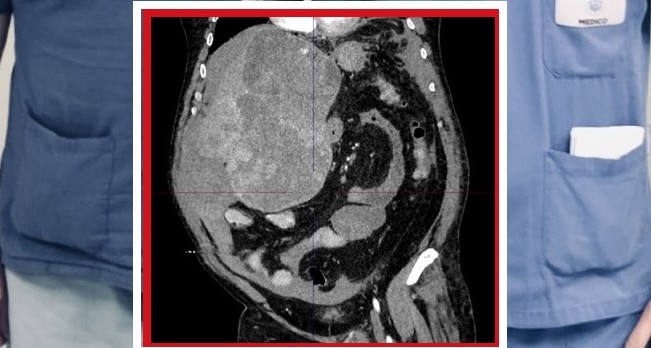

Chirurgia epatica estrema al Policlinico di Bari per l’asportazione di un tumore di quasi 5 kg e 30 cm di diametro, che occupava più della metà dell’addome in un paziente di 60 anni. Un caso di estrema complessità, giunto in urgenza con un’emorragia epatica in atto, che ha richiesto il coinvolgimento di equipe multidisciplinari per salvare la vita del paziente.

L’uomo è arrivato con un’anemizzazione severa da tumore epatico gigante e sanguinante ed è stato preso in carico dalla chirurgia generale universitaria “V. Bonomo” del Policlinico di Bari, diretta dal prof. Mario Testini, di turno per le urgenze per il trattamento del caso.

Una volta stabilizzato è stato possibile eseguire l’epatectomia sinistra allargata, intervento chirurgico eseguito dall’equipe del prof. Testini, primo operatore il dott. Piercarmine Panzera con la dott.ssa Arianna Pontrelli, per asportare la grossa massa tumorale e parte del fegato.